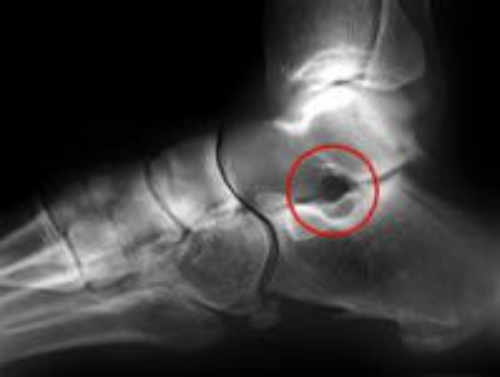

Seno Del Tarso anormal en pie plano flexible

Seno Del Tarso Anormal